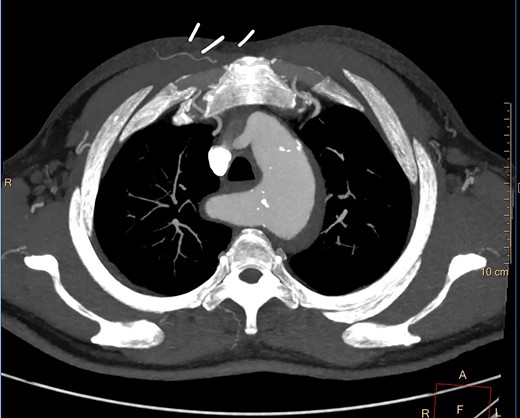

Despite optimal anti-impulse therapy, the patient had refractory chest/upper back pain. The patient underwent a left C-S bypass and right subclavian to common carotid artery transposition (with oversewing of proximal subclavian stump). This was followed by deployment of covered thoracic endovascular graft (Navion, Medtronic) from left common carotid artery (CCA) to 5 cm proximal to celiac artery proximally. The left subclavian artery was occluded using endovascular plugs. His postoperative 2-week CT showed good stent apposition and no endoleak (Fig. 4A, B). He was discharged Day 14 and returned to regular work at 1-month time interval.

(A) 3D-CT reconstruction showing post op repair and Right subclavian to carotid transposition. (B) 3D-CT reconstruction showing post op repair and left C-S bypass.